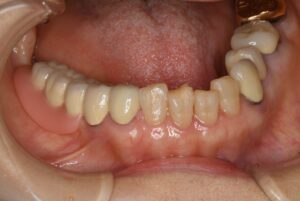

ケース1:右下奥歯3本を失った70代女性

当初は保険のクラスプ義歯を入れていましたが、動いて痛く、しっかり噛めないという訴えがありました。インプラントは希望されなかったため、テレスコープ義歯に変更。結果として右側でも硬いものが噛めるようになりました。写真の左は外したところ、右は装着したところです。手前2本の歯に内冠を作り、セメントでかぶせてあります。

この内冠に合わせて外冠が作られ、外冠の内面にはPEEK(ポリエーテルエーテルケトン)という耐久性の高い樹脂が貼られています。これが維持装置として働きます。